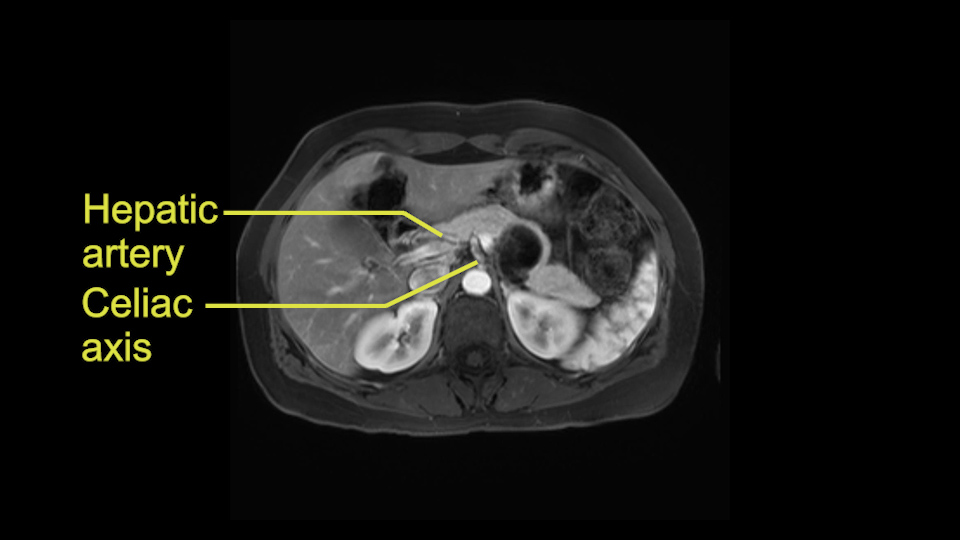

The second slowing down moment or consideration I give to a distal pancreatectomy is the anatomy of the portal vein and the splenic artery. And so I look here and the anatomy is pretty straightforward. The splenic vein comes off normally and runs behind the pancreas and I can see the artery superior to that, again coming off in a normal manner from the celiac axis. So those two things, the portal vein and the splenic artery will be taken normally in this procedure.

I think the splenic vein, once I have slowly teased it off from the cyst and from the retropancreatic parenchyma, I would put a vessel loop around it to serve as a traction. So once you have the vessel loop or probably umbilical tape, to retract or pull the pancreatic parenchyma while we slowly tease it off and try to move superiorly to be able to expose the splenic artery. That is again another slow-down moment because sometimes we think that it is the splenic artery at the superior edge of the pancreas, but it could also be the hepatic artery as it branches from the celiac artery.

So unfortunately I cannot show you a coronal view but you can see it easily on this scan, going down first you see the celiac trunk and you see here, quite a nice distance between the celiac trunk and the beginning of the mucinous cyst. And if you go up here and follow down the portal vein confluence you also see a nice distance there.